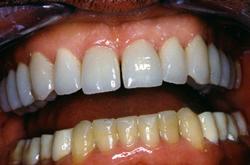

Couronnes céramo-céramiques. Réalisation prothétique Claude VALTIN (Paris).

Les 14 couronnes supérieures céramo-céramiques sont collées.

Vue finale

Après avec augmentation de la DVO de 6 mm.